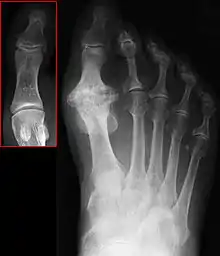

| Hallux not labeled but visible at upper left. | |

In 1988, Hattrup and Johnson described the following radiographic classification system:

- Grade I – mild changes with maintained joint space and minimal spurring.

- Grade II – moderate changes with narrowing of joint space, bony proliferation on the metatarsophalangeal head and phalanx and subchondral sclerosis or cyst.

- Grade III – severe changes with significant joint space narrowing, extensive bony proliferation and loose bodies or a dorsal ossicle.[3]